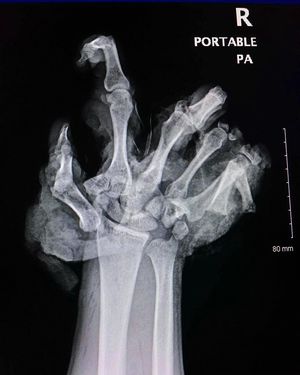

4th of July type of injuries! Be careful playing with fireworks tonight folks! The image here shows what happened when a firework exploded in a young man’s hand. As a result, he sustained extensive harm to the soft tissue and had a several finger amputations. Since fireworks are often used around holidays, injuries tend to cluster about holidays and can spoil them. Happy Independence Day America!